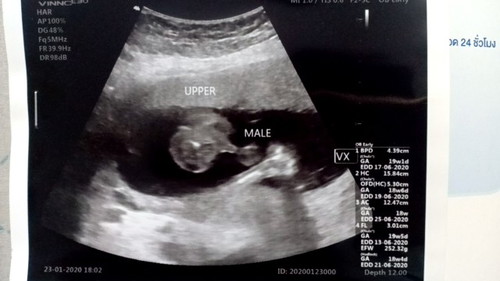

หมอรพ. ประกันสังคมบอกว่าได้ลูกผู้หญิง ตรวจ ตอนนั้น 17+4 weeks วันนี้ไปหาหมอที่ฝากครรภ์ หมอบอกได้ลูกชาย 19+3 Weeks อยากทราบว่าอายุครรภ์19+3 Weeks เพศของลูกชัดหรือยังหรือจะมีการเปลี่ยนแปลงได้อีก #ภาพอัลตร้าซาว์ด 19+3 Weeks

ชัดแล้วค่ะแม่ ขึ้นหน้าเครื่องซาวด์เลยว่าผู้ชาย